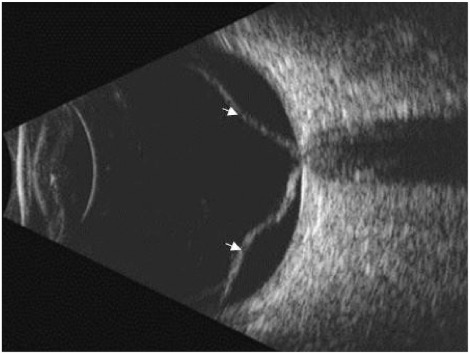

Posterior scleritis

Posterior scleritis on B-scan shows a characteristic “T-sign,” formed by fluid in the sub-Tenon’s space creating a hypoechoic area that joins the optic nerve shadow. The sclera may appear thickened, and there may be associated retinal or choroidal folds.